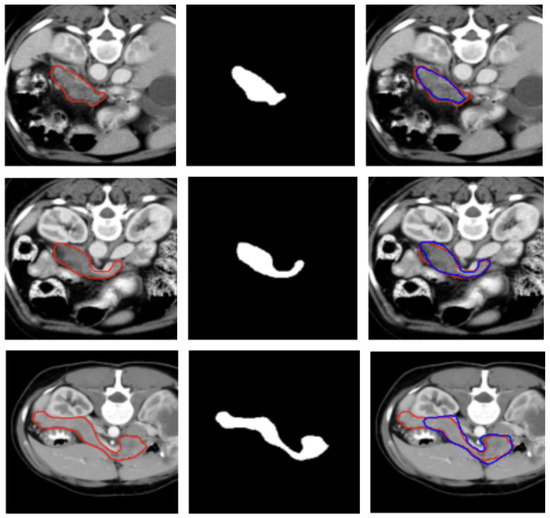

A visual representation of the segmentation obtained on a representative subject of the NIH dataset is illustrated in Figure 2.

Figure 2.

Visualization of two representative test samples from the NIH dataset showing: the input image with the pancreas ground truth overlaid as a red contour (left), the corresponding pancreas mask (center), and the output of the model overlaid to the input image as a blue contour (right). The first sample (first and second row) illustrates an easy case with clear organ boundaries and the second sample (bottom row) depicts a more challenging case with low contrast, yet the model still captures the main structure.

Figure 2 and Figure 3 show, qualitatively, the results of our attention-based 3D U-Net model trained on NIH and MSD datasets, respectively, with a combined Focal and Dice loss. The figures show across different sample cases, how the model successfully delineates the pancreas with high spatial accuracy, as demonstrated by the strong alignment between predicted and ground truth contours. The use of Dice loss contributed to the precise overlap in the segmented regions, while Focal loss improved the model sensitivity to challenging areas, especially along class boundaries where the pancreas is thin or adjacent to low-contrast structures. Notably, even in slices where the pancreas is partially obscured or appears small and fragmented, the model maintains accurate contour predictions. This suggests that the attention mechanism effectively focuses on relevant anatomical regions, suppressing background noise and enhancing feature discrimination.

These visual results support the quantitative performance of the model reported in Table 1 and Table 2 and demonstrate its ability to produce reliable and anatomically consistent pancreas segmentation in volumetric CT data.